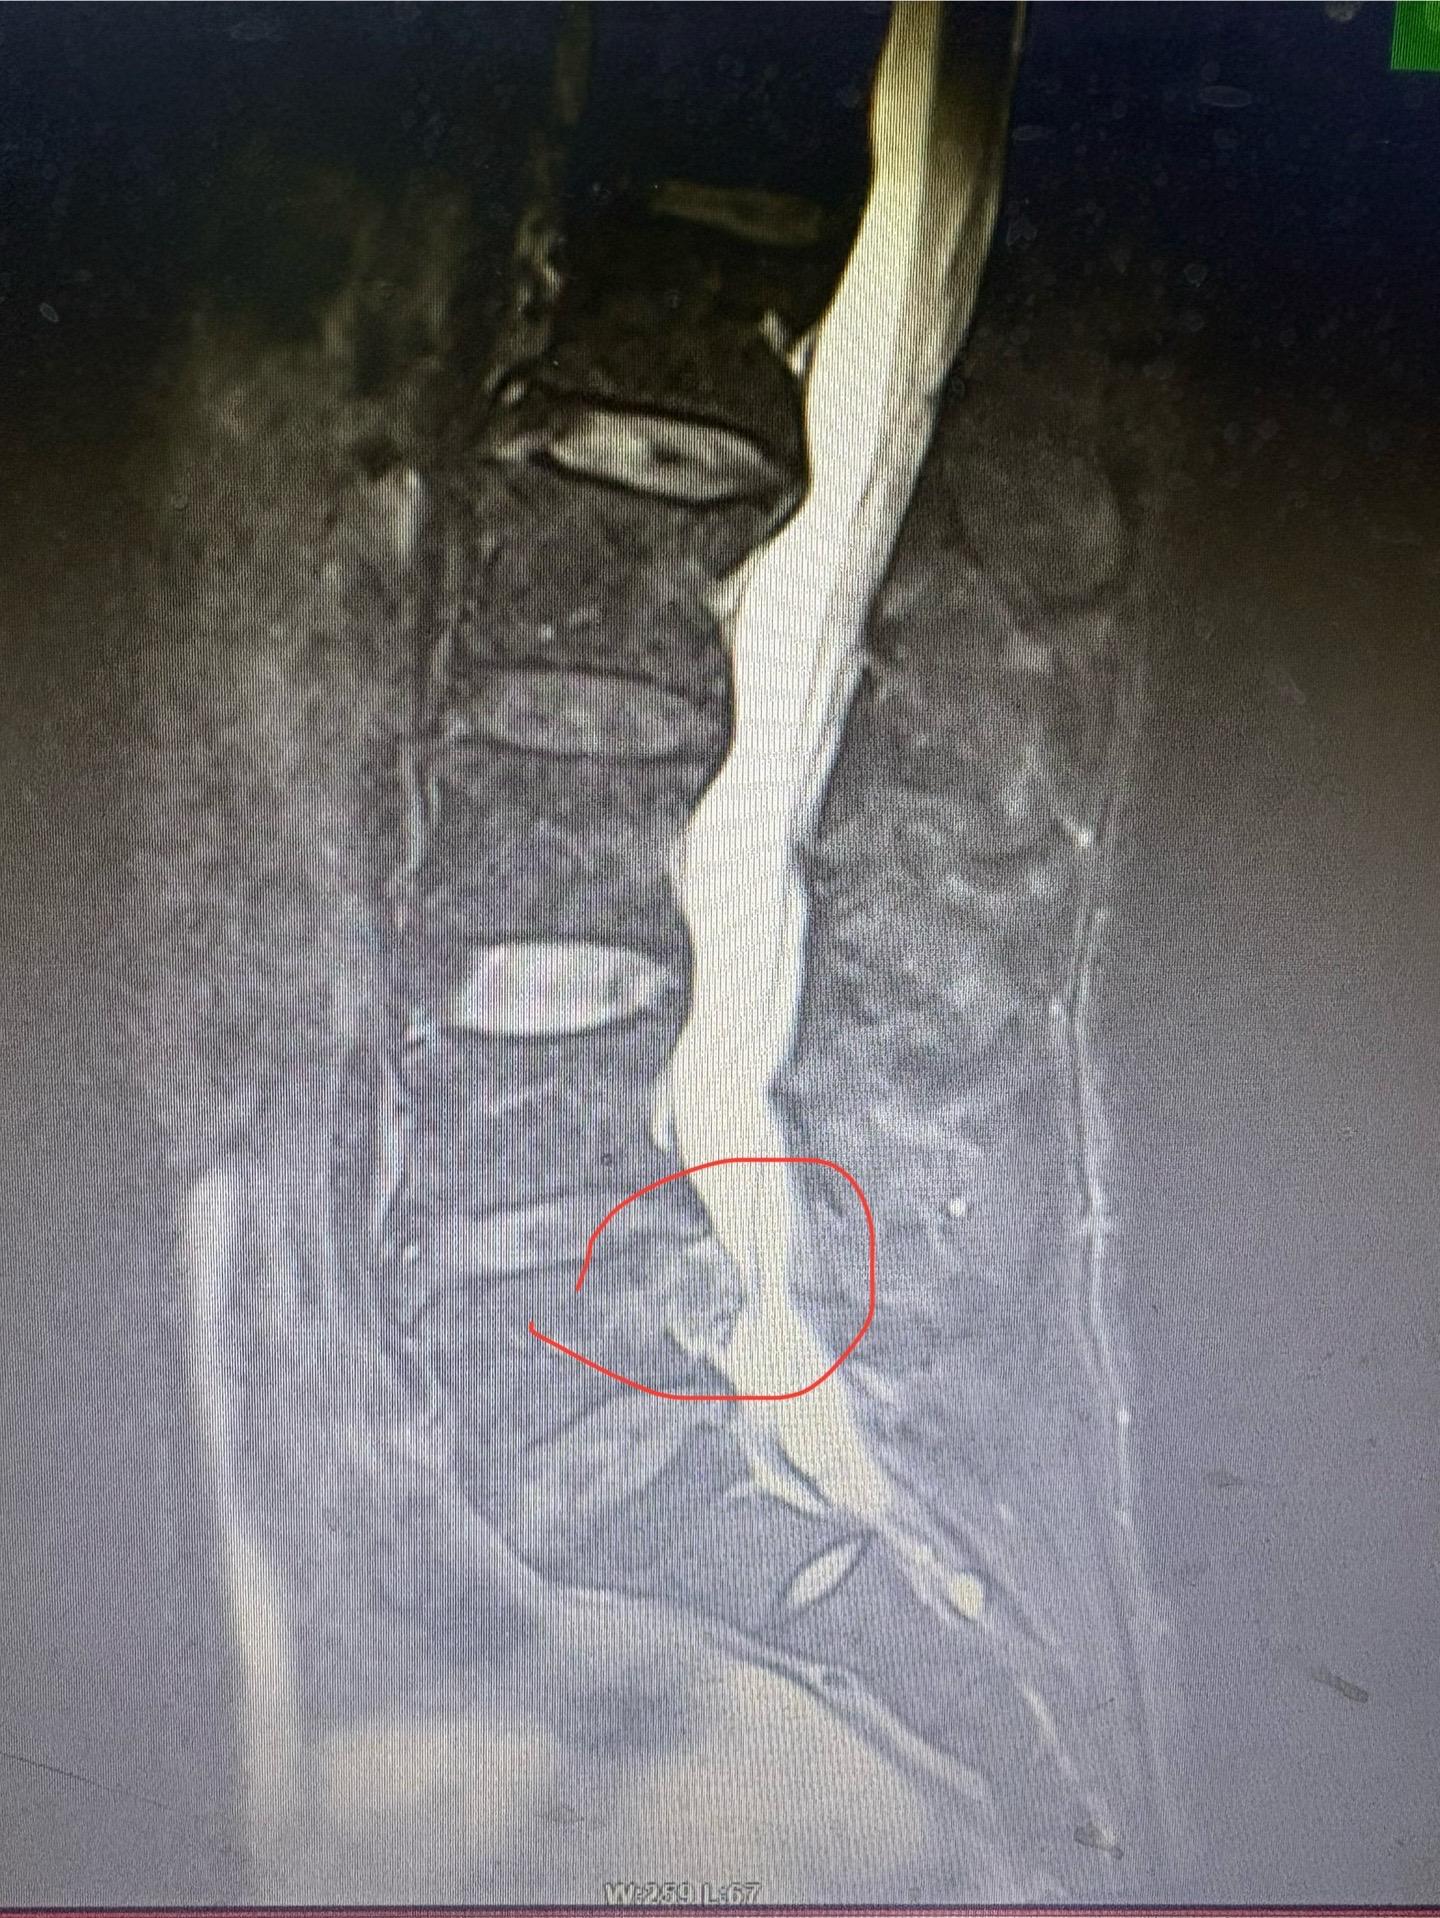

是肿物还是椎间盘?如果不出意外的话,应该是一块超大的椎间盘脱出

椎间盘脱出了能不能保守治疗?今天碰到一个病例,四年前椎间盘脱出,选择保...

椎间盘突出是常见问题,但是十一岁的椎间盘突出非常罕见,不懂小朋友经历了什么。